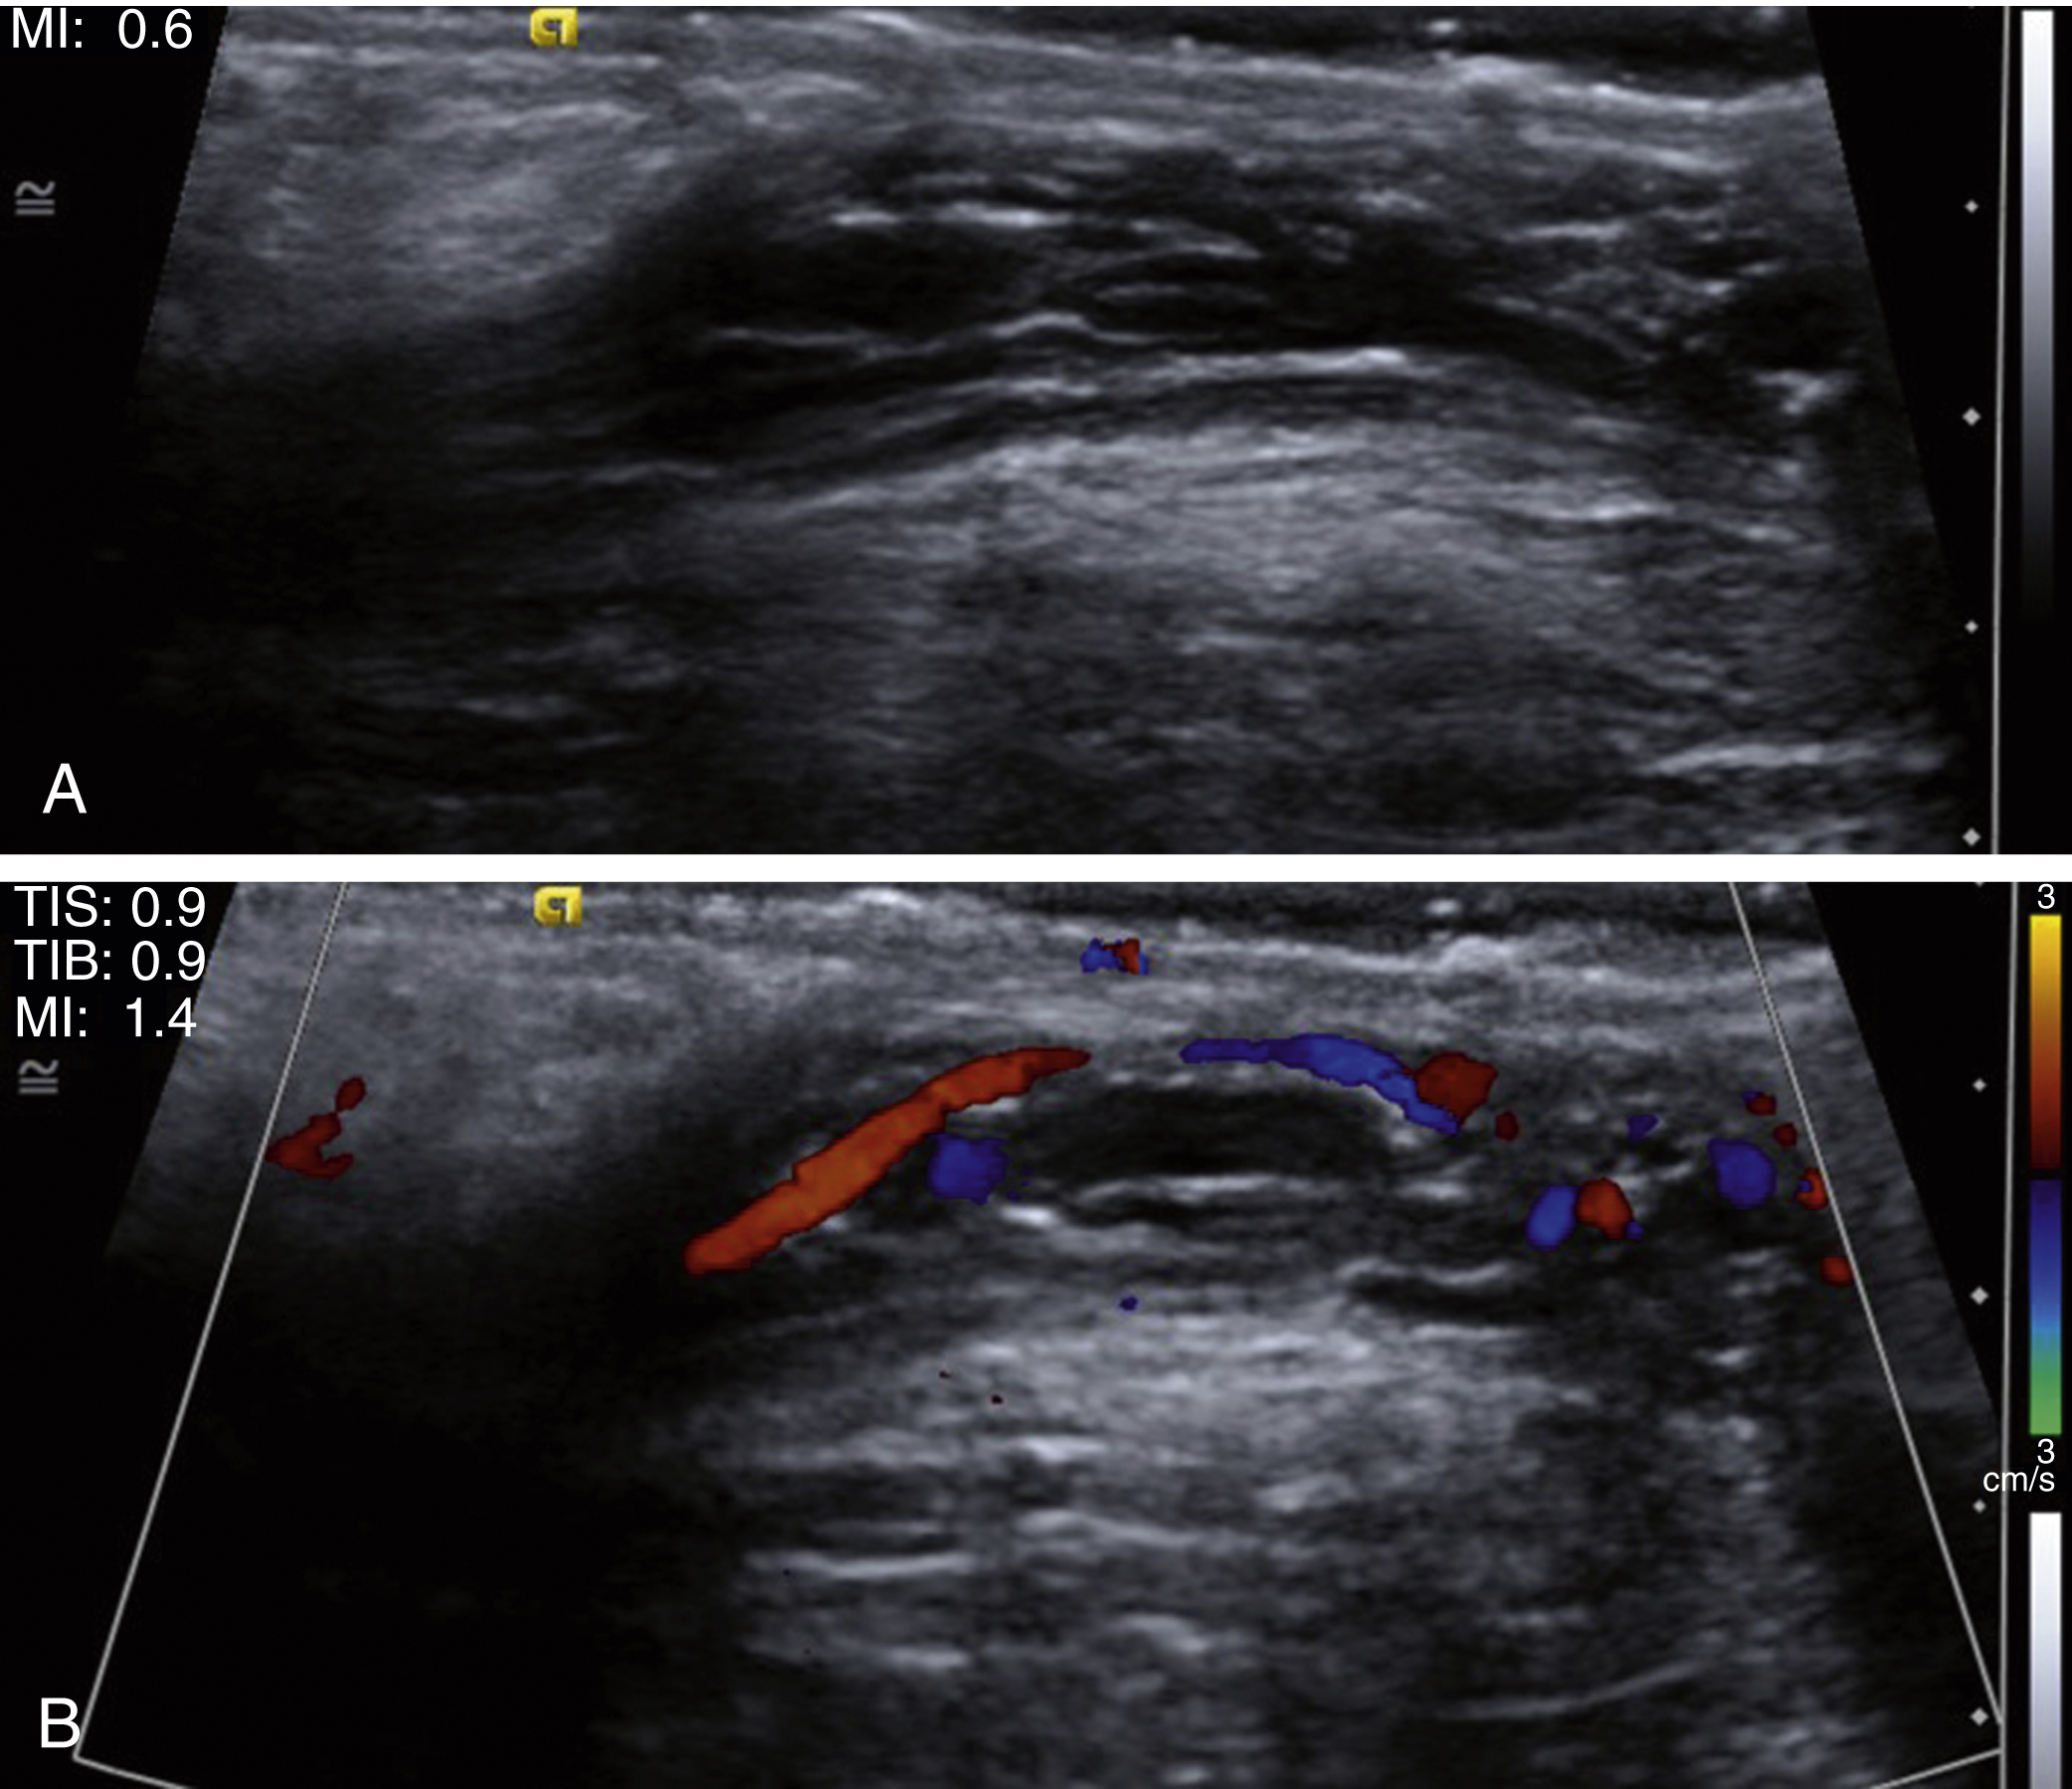

It is often challenging to get flow within the testicles of infants and small children. Often the children are not resting still or comfortably, which causes Doppler artifact. Occasionally the emergency department physicians may need to give medication to make a child more comfortable for the examination to be performed. If initial attempts at documenting vascularity to the testicles are not successful, color Doppler and spectral Doppler waveform analysis can be optimized by using a higher-frequency probe or decreasing color box interrogation dimensions ( Fig. 7.1 ).

Fig. 7.1, Optimizing Doppler.